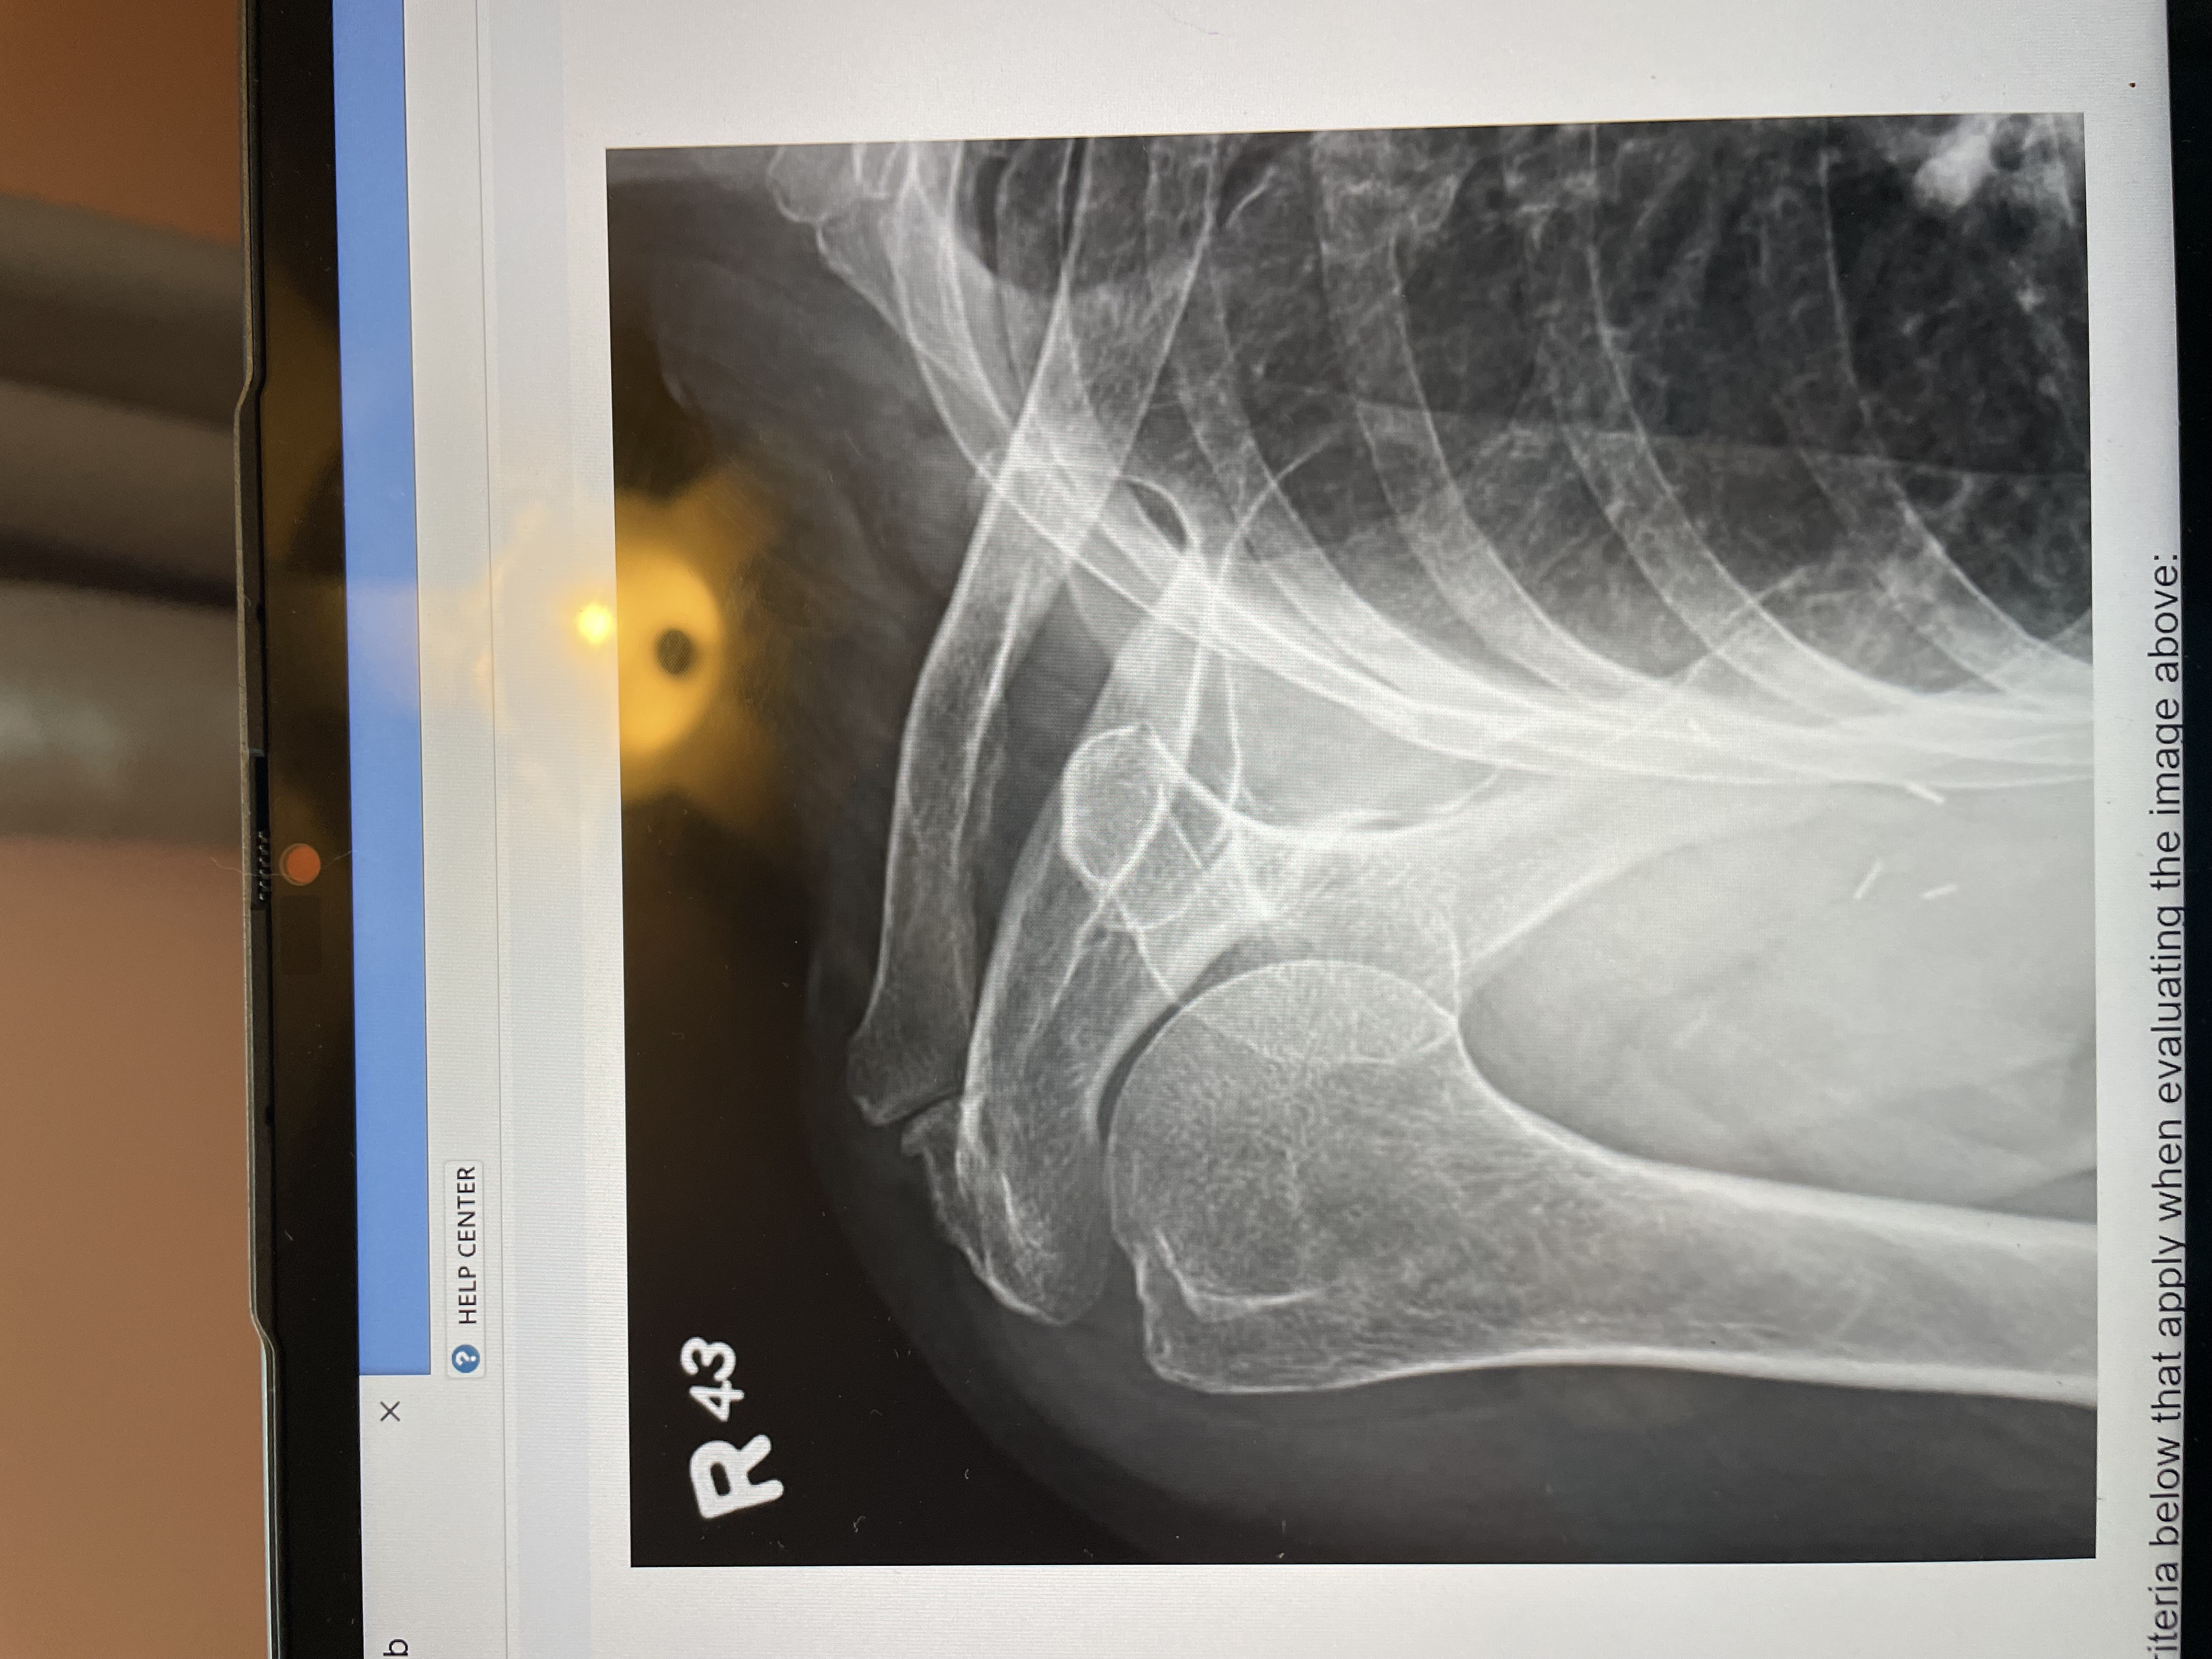

What is the required anatomical structures for an AP of the shoulder?

the entire proximal humerus, the scapula, the majority of the clavicle

(note this image doesnt’t have the full scapula so it wouldnt have everything required)

AP - internal rotation